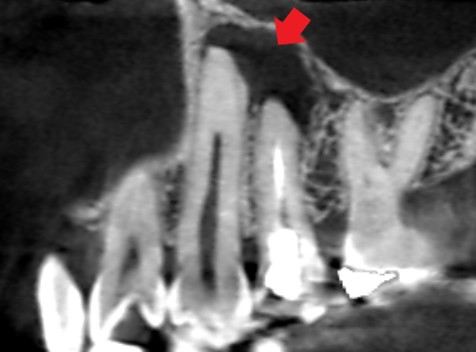

左上の犬歯と第一小臼歯のCT画像です。赤い矢印の先に、犬歯と第一小臼歯の両方の根の先にかかる大きな膿の影がみられます。